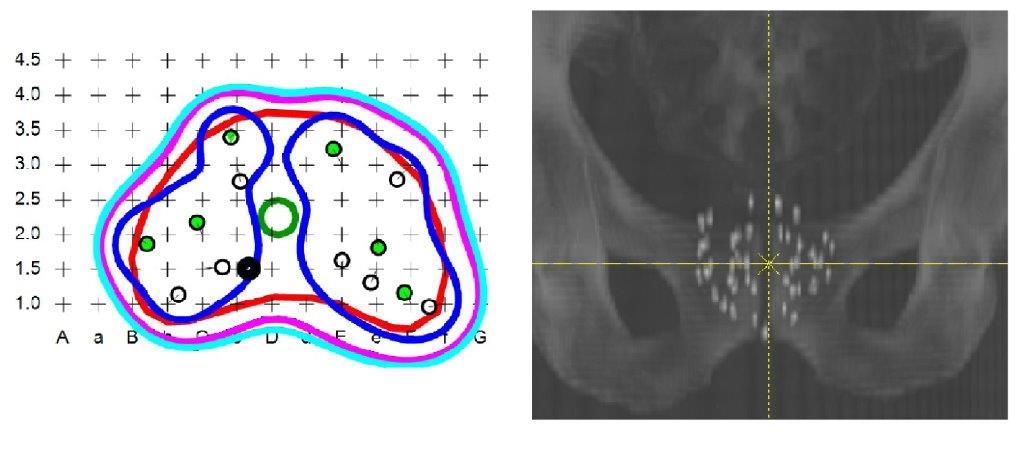

links: Bestrahlungsplan für die Seedimplantation.

rechts: Röntgenbild zur Lagekontrolle der Seeds.

Geeignete Patienten mit Prostatakrebs im frühen Stadium können hier auch eine Behandlung mit permanent eingebrachten radioaktiven Strahlern (SEED-Implantation) erhalten.